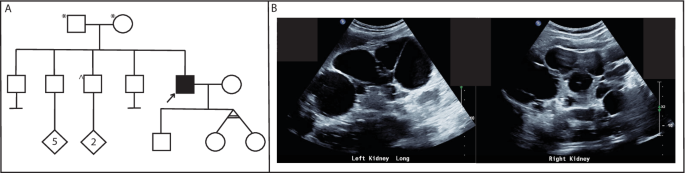

We identified via genome sequencing analysis a single nucleotide duplication within the PKD1 5′UTR, NM_001009944.3:c.−69dupG; NC_000016.10:g.2135757_2135758insC (Dec.2013: hg38, GRCh38) in a male proband (RBW402, supplementary Fig. 1) with a clinical diagnosis of ADPKD, without a significant family history (Fig. 2A). His parents had normal ultrasound examinations in their 60’s, but parental samples were not available to confirm whether this variant occurred de novo. His clinical history is consistent with typical ADPKD; he was diagnosed at 39 years old with >20 bilateral kidney cysts causing enlarged kidney lengths (19 cm left kidney length and 22 cm right kidney length), with liver cysts (Fig. 2B). Clinical ADPKD panel testing via short-read WGS (PKD1, PKD2, GANAB, HNF1B, TSC1, TSC, OFD1, UMOD, PKHD1), and targeted sequencing and MLPA of HNF1B did not identify a genetic cause of his ADPKD.

A Pedigree of RBW402, clinically diagnosed with ADPKD. No significant family history reported with parents having had normal ultrasound examinations in their 60 s. *normal ultrasound examination in 60’s. ^ normal ultrasound examination in 30’s. Arrow indicates proband (RBW402). B Kidney ultrasound images from RBW402 demonstrating bilateral kidney cysts.